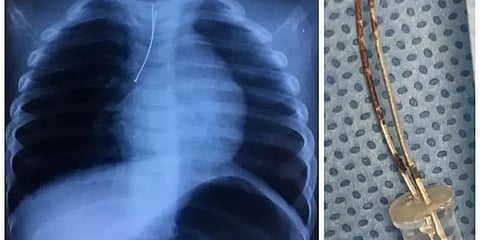

தெலுங்கானா மாநிலம் ஹைதராபாத் பகுதியை சேர்ந்த 9 வயது சிறுவன் ஒருவன் விளையாடி கொண்டிருந்தபோது விளையாட்டுத்தனமாக எல்.இ.டி பல்பு ஒன்றை விழுங்கிவிட்டான். இந்த பல்பு நுரையீரல் பாதையில் சென்று சிக்கியதால் மூச்சுத்திணறலால் சிறுவன் அவதிப்பட்டுள்ளான்.

இதையடுத்து சிறுவனை அவனது பெற்றோர் உடனடியாக மருத்துவமனையில் அனுமதித்தனர். மருத்துவர்கள் அந்த பல்பை அறுவை சிகிச்சை மூலம் அகற்றி சிறுவனின் உயிரை காப்பாற்றினர். தற்போது சிறுவன் நலமுடன் இருப்பதாக தகவல் வெளியாகியுள்ளது.